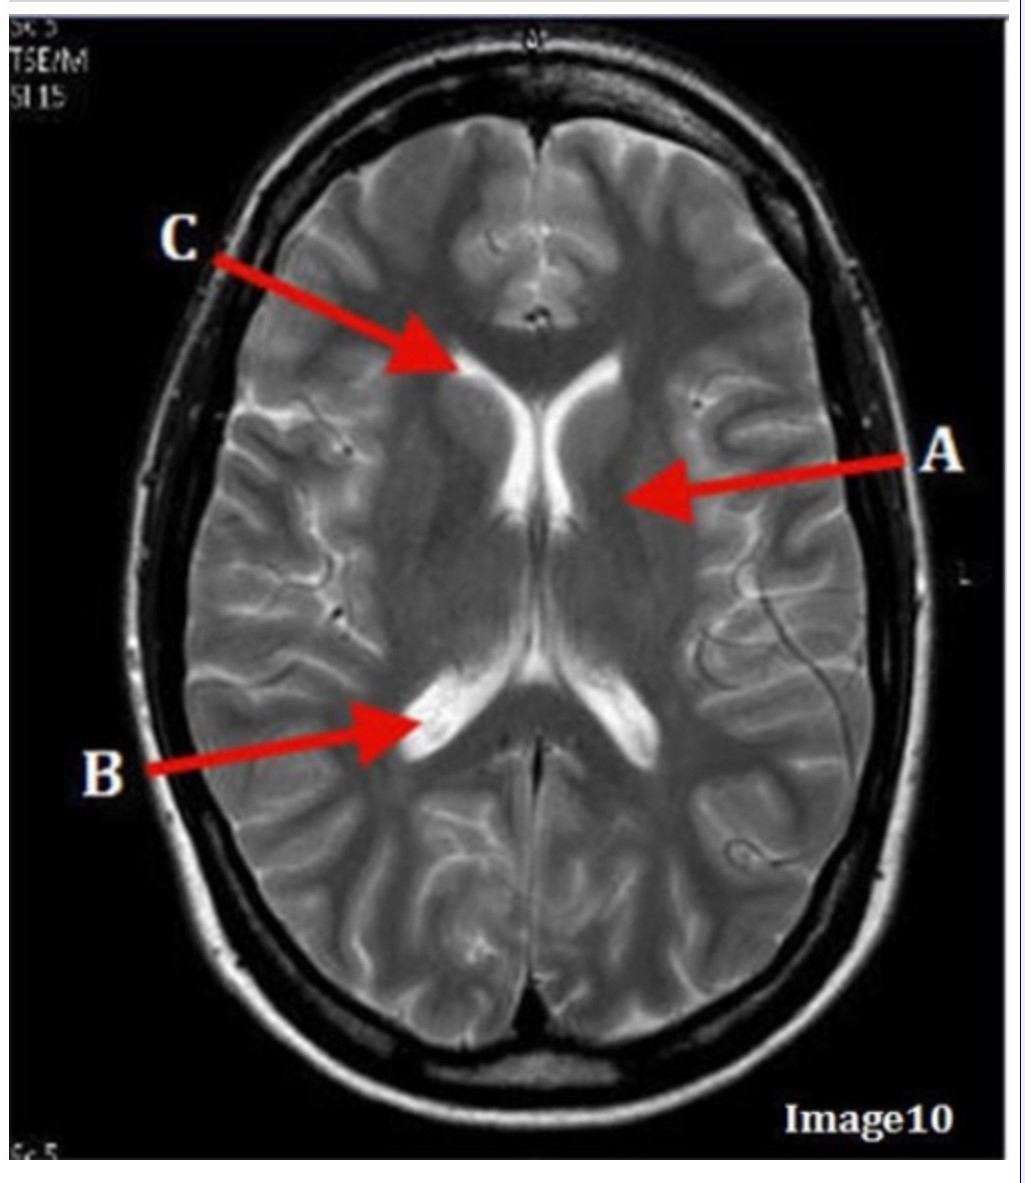

Letter B in Image 10 is pointing to:

A. Third ventricle

B. Basal ganglia

C. Anterior horn lateral ventricle

D. Posterior horn lateral ventricle

Letter C in Image 10 is pointing to:

A. Third ventricle

B. Basal ganglia

C. Anterior horn lateral ventricle

D. Posterior horn lateral ventricle

Letter A in Image 10 is pointing to:

A. Third ventricle

B. Basal ganglia

C. Anterior horn lateral ventricle

D. Posterior horn lateral ventricle